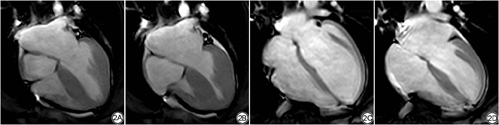

HHD组LAEF、LVEF均低于对照组(图1、2),LAEDV、LAESV、LVEDV、LVESV高于对照组,具体数据见表2。LGE示4例HHD患者存在条状或小片状延迟强化,而12例HHD患者未见确切延迟强化。其中10例出现二尖瓣返流,4例出现主动脉瓣返流,1例出现心肌脂肪浸润,未出现心肌梗死病例。

左心室射血分数(left ventricular ejection fraction, LVEF):将心脏短轴电影导入CVI42的心功能分析模块,通过软件自动识别心内膜和心外膜,并经人工校正后获得左心室舒张末期容积(left ventricular end-diastolic volume, LVEDV)、左心室收缩末期容积(left ventricular end-systolic volume, LVESV)、LVEF。